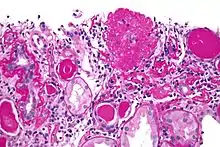

| Light micrograph of focal segmental glomerulosclerosis, hilar variant. Kidney biopsy. PAS stain. | |

On histology, FSGS manifests as damage (sclerosis) to segments of glomeruli; moreover, only a portion of glomeruli are affected.[18][19] The focal and segmental nature of disease seen on histology help to distinguish FSGS from other types of glomerular sclerosis.[19]

Diagnosis of FSGS is made by renal biopsy that includes at least 15 serial cuts with at least 8 glomeruli.[29][30] Histologic features include sclerosis (scarring) of a portion (average: 15%) of the glomerular space, with only a portion of glomeruli manifesting any sclerosis.[30]